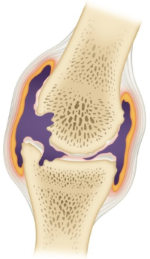

사진 출처 - 네이버 지식백과

위의 그림은 류마티스가 순차적으로 진행되는 상태를 나타냅니다. 첫번째 초기단계는 관절낭 안쪽 활막에 염증이 생긴 상태입니다. 중간으로 접어들면서 관절이 붓고 물이 차며 연골이 손상됩니다. 결국 후기로 가면 섬유화가 일어나 뼈와 뼈가 붙어버리는 최악의 경우가 발생하게 됩니다.